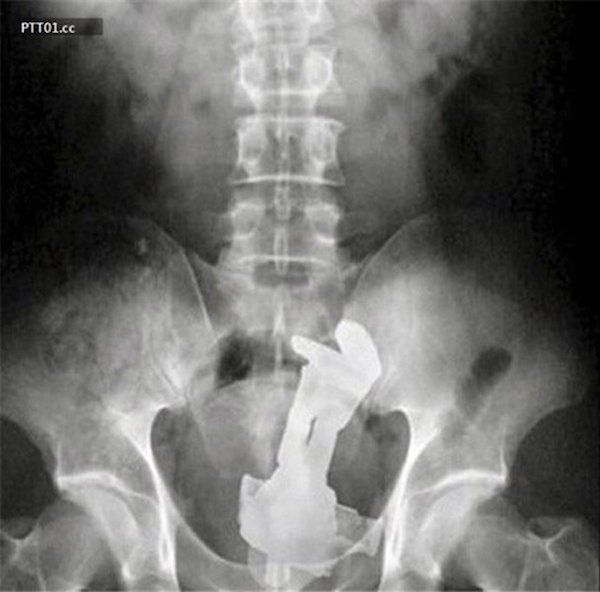

/ 15Agrafka

Dzieci i zwierzęta jedzą różne rzeczy. Idorosłym przytrafia się sytuacja, kiedy połkną coś, czego nie powinni. Na przykład agrafkę. Aż boli, jak się na to patrzy.